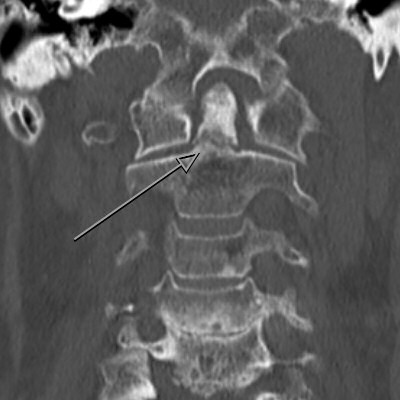

Exempel på dens-fraktur typ 2 före och efter fixation.